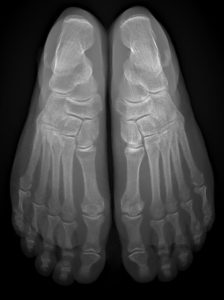

Il s’agit d’un appareil type cone beam permettant d’étudier en position débout, comme un scanner, les pieds, les chevilles et les genoux avec une très faible irradiation du patient comparé à un scanner conventionnel.

Il se destine aux pathologies liées aux troubles posturaux, aux douleurs des avants et arrières pieds.

Sa finesse d’image lui permet aussi d’être au cœur des bilans traumatiques et rhumatismaux de la cheville et du coup de pied.